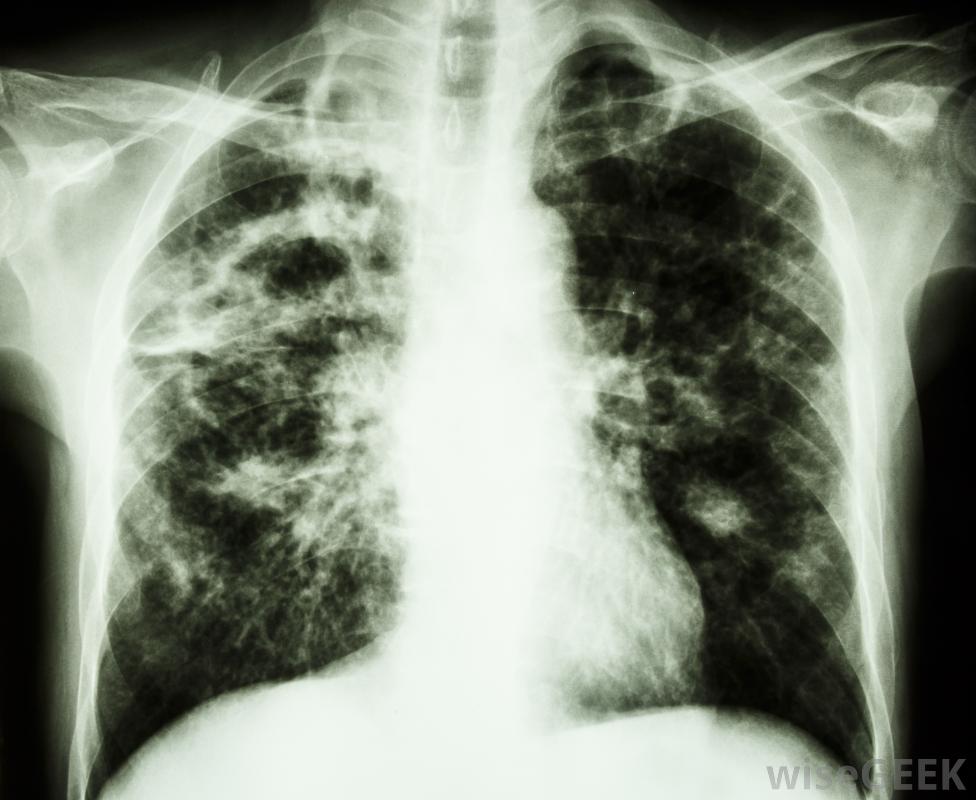

胸腔积液是胸腔内多余液体的积聚,胸腔包围着肺部。正常情况下,胸膜中含有一层薄薄的液体,以保持肺部在呼吸过程中的平稳运动。当有过多液体时,右侧胸腔积液发生在右侧胸膜中,右侧胸腔积液比左侧胸腔积液更容易导致充血性心力衰竭胸腔积液。右侧胸腔积液或右侧胸腔积液的发生,是一种潜在疾病的结果。右侧和左侧胸腔的液位通常不同,称为非对称性胸腔积液。胸腔积液也可孤立于其中一个空洞,称为单侧胸腔积液。右胸腔积液主要与充血性心力衰竭(CHF)有关胸腔积液是胸腔积液在肺部周围胸腔中的积聚。胸腔积液的最初症状通常是当胸腔中的液体达到一定量时大约500毫升。报告的症状包括呼吸困难或疼痛,以及呼吸时胸壁的运动减弱。当胸部和背部被交叉或轻拍时,共振也会减少当用听诊器检查时,呼吸音可能会很迟钝,也可能会有不寻常的声音,如噼啪声或摩擦声,这是由于过多的液体产生的摩擦造成的。如果怀疑这些症状,通常会进行x光或超声波检查以确认诊断

某些心脏疾病,如右胸腔积液,可以用超声波检测出来任何类型的胸腔积液的治疗都是基于根本原因,必须治疗才能解决整个问题。为了减少胸腔积液,会用针头将多余的液体抽出。当积液较多时,可以使用引流管或进行手术。其他治疗方法包括使用化学药品治疗感染和手术融合胸膜腔以阻止液体积聚。